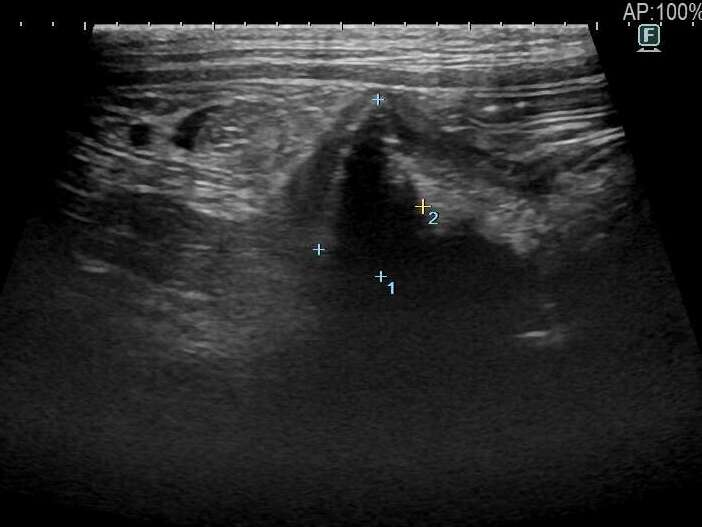

血液検査では正常値が得られましたが、X線検査では異常なガス貯留が認められました。また、腹部超音波検査では消化管に異物を疑うような所見が得られました。

消化管内に異物を疑う所見

通常消化管内異物による腸の完全閉塞の場合、詰まっている部位から手前の腸は内容物で渋滞し拡張するという特徴的な超音波画像所見が認められます。しかし、本症例では異物は疑われたものの、消化管の拡張所見は乏しく完全閉塞との判断が難しく、手術を行うか悩ましい状況でした。